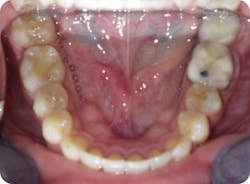

- He measured 28 mm, which is very narrow considering that uncrowded adults measure 35 mm–39 mm.

- He had improper buccolingual inclination as most of the posterior teeth had excess lingual inclination (figure 4).